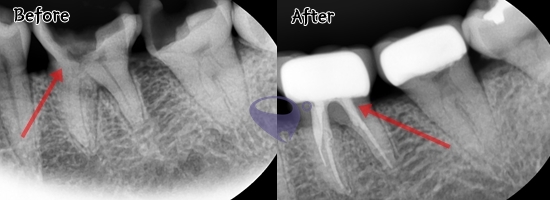

#患者三 为了蛀牙需要的 #一般根管治疗